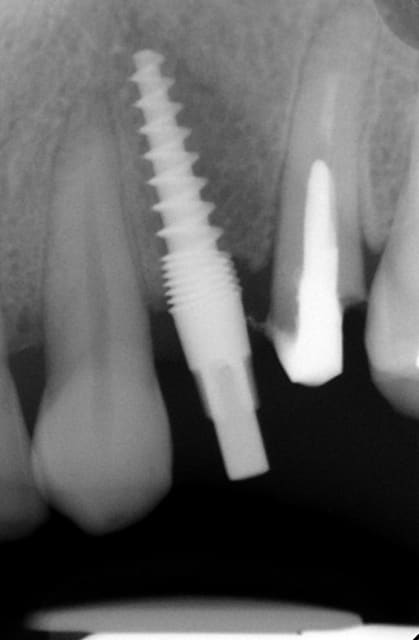

Oui ca semble ....sur la opg radio tu peux voir la situation seulement deux semaines après l´implantation immédiate 34 jusqu´à 36 et 45, les derniers 2 photos montrent la même situation après un an ( où on a enlevé la supra construction pour un contrôle). Sur ce cas je voulais montrer la bonne régénération osseuse et de la gencive.

Oui,c´est un Prep cap zircone , que je cémente juste après l´implantation immédiate pour mieux former la gencive. Les implants monoblocs ont étés implantés entre 40 et 60 Ncm . Les photos 6 et 8 on voit les prep cap juste après l´implantation immédiate ce sont des sortes de "couronnes" pré fabriquées.

Oui , tu as raison pour la 45, en fait quand j´ai enlevé la 45 j´ai choisi l´axe comme ca ( dans l´os dur et en bon santé) parce que c´etait ici que je pouvais avoir la stabilité ( pour cet implant à 50 Ncm.

Voilà une patiente que je revois à deux ans apres la pose d'un monobloc Classic line 3,5/12mm et prep cap zircone 12 degres 2/2 en 24.

Radios 1,2,3 photo 1= jour de la pose de l'implant.

radio 4 photo 2 et 3= 8 semaines post pose de l'implant, ceramiques scéllées.

Radio 6, photo 4 et 5 controle à 24 mois.

Deux ans plus tard, la gencive a recouvert la zircone et on observe à la radio un gain osseux au niveau des micros spires.